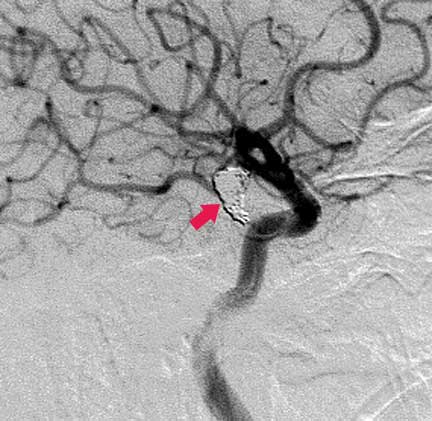

CASO 2 : Embolización endovascular con microespiras (coils) en paciente joven con hemorragia intracraneal y parálisis de nervio oculomotor

Antes de la embolización:

Después de la embolización: